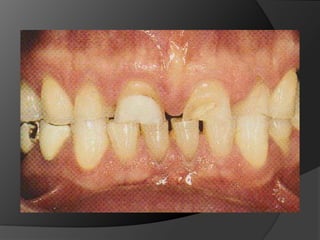

fundamentos de periodoncia en prótesis fijaEl éxito de una prótesis no es medida solamente en el acto de la cementación, sino también a lo largo del tiempo, por estar integrada y en armonía con la estética, tejidos pulpares, tejidos periodontales, músculos y articulación temporomandibular.1

fundamentos de periodoncia en rehabilitaciónEs incuestionable que la salud del periodonto deba ser restablecida antes de cualquier tratamiento restauradorEl paciente es responsable en gran medida del mantenimiento de su salud bucal

El análisis para seleccionar la ubicación de la línea de terminación se enfoca en 2 componentes:Estética vs HigieneExtensión mínima dentro del surco gingivalDisimular la zona de asentamientoFacilitar la higiene del pacienteNecesidad de aumentar la retención y estabilidadLínea de Sonrisa